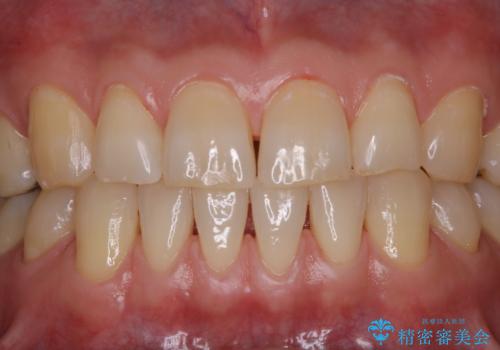

タバコとコーヒーによる頑固な着色落とし

また、仕上げのトリートメントでは歯の表面の凸凹にミネラルを補給して、ツルツルの表面に仕上げます。定期的にPMTCを行うことにより、歯質の強化になり着色がつきにくい状態になります。

普段の飲食物・歯磨き・生活習慣などにより着色の付き具合には個人差があります。どれくらいの頻度で行うことがベストかは、その都度担当の歯科衛生士とご相談します。